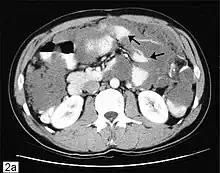

| Computed tomographic scan of an abdomen showing pseudomyxoma peritonei with multiple peritoneal masses (arrow) with "scalloping effect" seen. | |